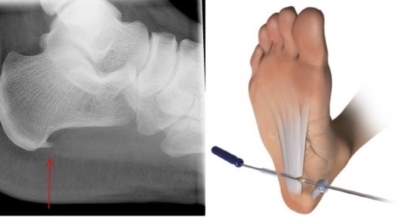

발뒤꿈치뼈 전내측 종골 결절 부위의 명확한 압통점을 찾으면 진단이 가능하고 족저 근막의 방향을 따라 발바닥에 전반적인 통증을 보이는 것을 확인할 수도 있습니다. 발가락을 발등 쪽으로 구부리거나 환자가 발뒤꿈치를 들고 서 보게 하여 통증이 증가되는 것을 보는 것이 진단에 도움됩니다. 증상이 전형적인 족저 근막염의 양상이 아니거나 적절한 치료에도 호전이 없는 경우 다른 질환의 감별 진단을 위하여 엑스레이 검사, CT, MRI, 근전도 검사 등을 시행하게 됩니다.

비수술적 치료로 대부분 족저 근막염 증상이 나아질 수 있지만 일부 환자는 수술이 필요한 경우가 있습니다. 수개월간의 비수술적 치료를 했음에도 발 통증이 계속되면 수술을 고려해봐야 하는데요 수술을 통해 족저 근막을 늘려주는 방법을 고려해 볼 수 있습니다. 최근 관절경을 이용하여 족저 근막 절개술을 시도하기도 하는데 수술적 치료의 성공률은 70~90%로 높게 알려져 있다고 합니다. 하지만 수술 후 신경 손상 등의 합병증이 유발될 수 있으므로 잘 알아보고 수술을 결정하시는 게 좋겠습니다.